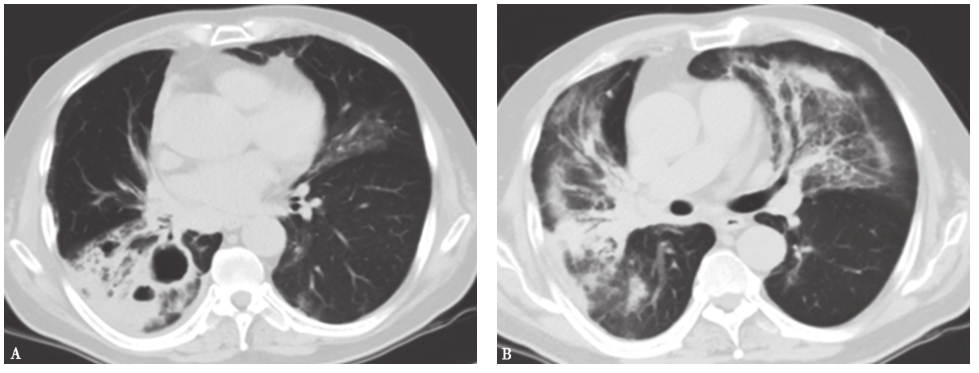

(4)结缔组织疾病相关间质性肺疾病:结缔组织疾病(CTD)是一组异质性、免疫介导、可累及多个器官的炎症性病变,主要包括类风湿关节炎(rheumatoid arthritis,RA)、系统性红斑狼疮(systemic lupus erythematosus,SLE)、 多发性肌炎(polymyositis,PM)/皮肌炎(dermatomyositis,DM)、系统性硬化症(systemic sclerosis,SSc)、干燥综合征(Sjogren syndrome,SS)等。CTD的主要病理改变为疏松结缔组织发生黏液性水肿、类纤维蛋白变性、小血管坏死和组织损伤。肺支气管、肺血管及肺间质及胸膜含有丰富的结缔组织,因而成为重要的靶器官。CTD累及肺部的表现有间质性肺疾病、细支气管炎、肺血管病变及肺实质小结节等。病理类型可有普通型间质性肺炎、非特异性间质性肺炎、淋巴细胞间质性肺炎、机化性肺炎等。不同的病理类型有不同的HRCT表现(图4)。临床表现不仅有原发疾病表现也有肺部表现,诊断需要完善自身免疫相关疾病的诊断,必要时需要肺活检明确组织病理学类型,对于制订有效的治疗方案和判断患者预后至关重要。

图4皮肌炎合并机化性肺炎胸部CT表现

女性患者,46岁,活动后气喘1个月。胸部CT可见双肺磨玻璃高密度影伴实变病灶,沿支气管血管束走行分布。病理诊断为皮肌炎合并机化性肺炎